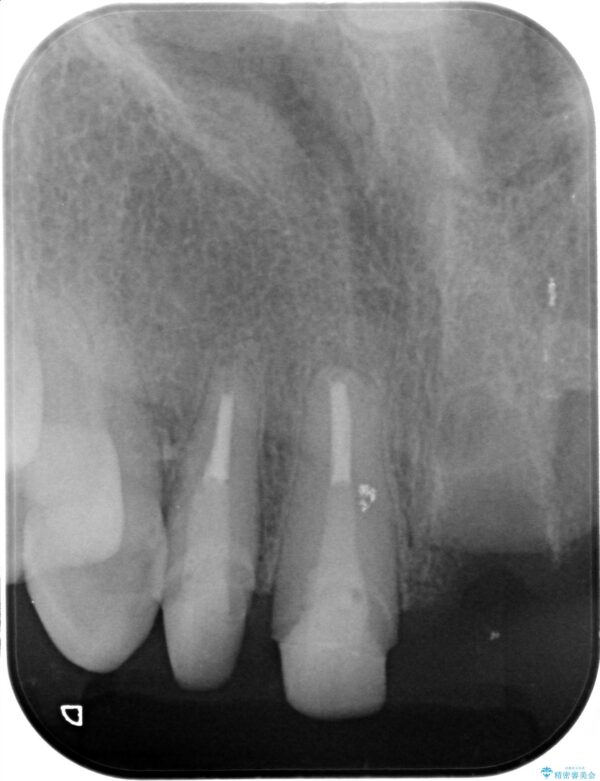

一見して問題ないように見える左側の2前歯は、セラミックを除去してみると亀裂や虫歯の再発が見られました。

抜歯時に可及的に歯肉のボリュームを保つよう骨充填材とコラーゲン製剤による填塞を行い審美的かつ機能的なブリッジとなるよう治療を進めます。

治療前

歯槽堤保存術を併用したブリッジ治療 治療前画像 歯槽堤保存術を併用したブリッジ治療 治療前画像 歯槽堤保存術を併用したブリッジ治療 治療前画像 歯槽堤保存術を併用したブリッジ治療 治療前画像 歯槽堤保存術を併用したブリッジ治療 治療前画像 歯槽堤保存術を併用したブリッジ治療 治療前画像 歯槽堤保存術を併用したブリッジ治療 治療前画像 歯槽堤保存術を併用したブリッジ治療 治療前画像 歯槽堤保存術を併用したブリッジ治療 治療前画像 歯槽堤保存術を併用したブリッジ治療 治療前画像